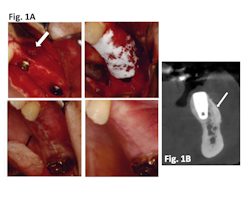

Clinical results: In a case series of 20 patients who received guided bone regeneration (GBR) with CelGro™, investigators observed mature, corticalized bone with fully integrated graft material in all patients within three to five months (Fig. 1).

Figure 1A: Defect (arrow) with implant pre-GBR; CelGro™ in place over void filler and implant; wound closure at baseline; wound 4 weeks post-GBR. Images represented are from a single trial participant.

Figure 1B: CBCT scan after GBR with CelGro™ at 6 months in an individual trial participant. Increased density of medullary bone around implant fixture (arrow) is consistent with a healing response. Progressive consolidation and fusion of GBR to the buccal cortex on either side of the edentulous segment of the left mandible. Analyzed using DICOM software.